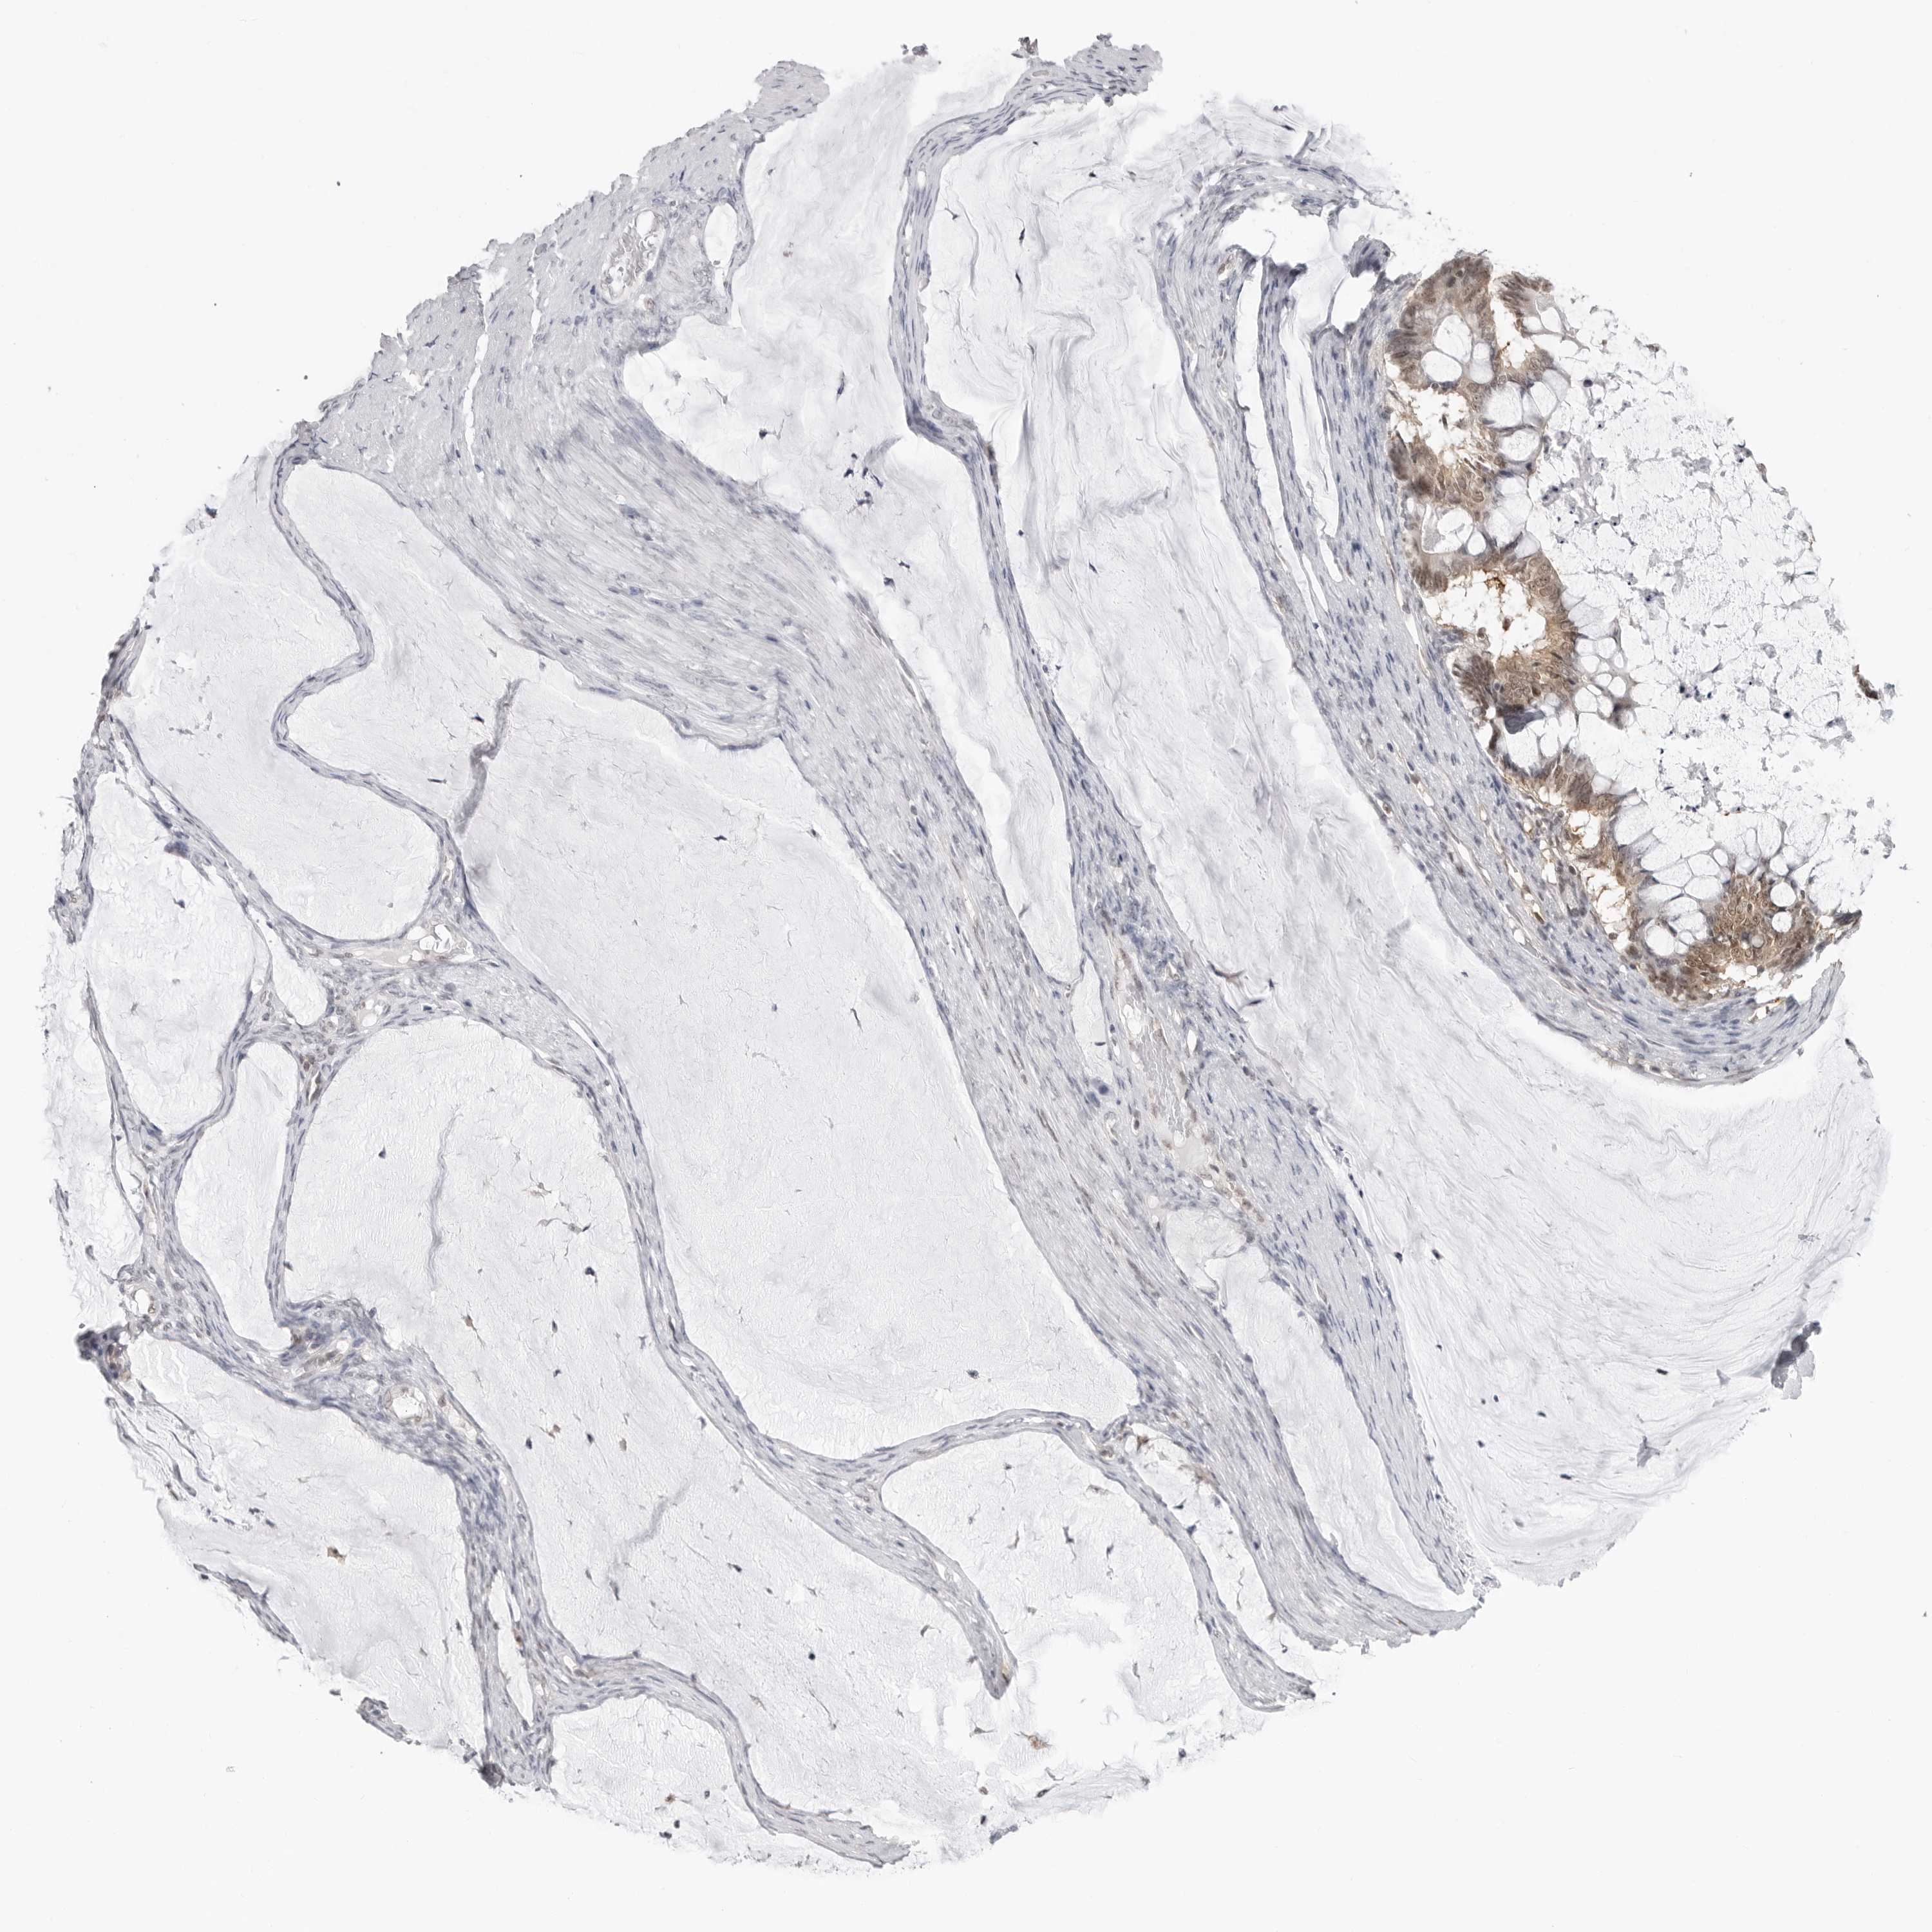

OVARIAN CANCER - Protein expressioni

A mouse-over function shows sample information and annotation data. Click on an image to view it in a full screen mode. Samples can be filtered based on level of antibody staining by selecting one or several of the following categories: high, medium, low and not detected. The assay and annotation is described here.

Note that samples used for immunohistochemistry by the Human Protein Atlas do not correspond to samples in the TCGA dataset.

Antibody stainingi

Antibody staining in the annotated cell types in the current human tissue is reported as not detected, low, medium, or high, based on conventional immunohistochemistry profiling in selected tissues. This score is based on the combination of the staining intensity and fraction of stained cells.

Each image is clickable and will lead to virtual microscopy that enables deeper exploration of all samples and also displays staining intensity scores, fraction scores and subcellular localization as well as patient and tissue information for each sample.

Antibody HPA026918

Antibody CAB013274

Antibody CAB018389

Staining

High

Medium

Low

Not detected

Carcinoma, endometroid